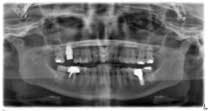

A 53-year-old female with a medical history of hypothyroidism, seasonal allergies, and asthma taking Synthroid and Singula presented to my office with pain in No. 3, failed root canal therapy, and a fracture. The tooth was deemed hopeless and extraction and implant placement was treatment planned. Under local anesthesia, tooth No. 3 was sectioned into three pieces and extracted. The sockets were debrided, filled with gel foam, and closed with chromic gut sutures. Healing was uneventful. The patient did not return for two years for follow-up. A CT scan was taken, which confirmed that approximately5 mm of bone remained below the floor of the sinus. After reviewing the options with the patient, a treatment plan of an internal sinus lift (osteotome), bone graft, platelet-rich fibrin (PRF) and simultaneous implant placement was agreed upon. Under local anesthesia, a full thickness flap with two vertical releasing incisions was performed at tooth No. 3 site. A trephine bur was used to a depth of 4 mm. An osteotome was then employed to infracture the bone core, which remained attached to the Schneiderman membrane. A bone graft consisting of DFDBA, anorganic bovine bone, and PRF was used in the osteotomy to increase the vertical bone height using sequential osteotomes. After sufficient elevation, a 7x9 tapered implant was placed on low speed to 50% of the implant depth. The remaining placement of implant was done with a hand torque on 50 ncm to allow for further expansion of the alveolar housing. A healing abutment was placed using the principles of platform switching. Healing was uneventful, and integration was successful.

Case 1: Implant and osteotome bone graft through the socket with Southern Implant